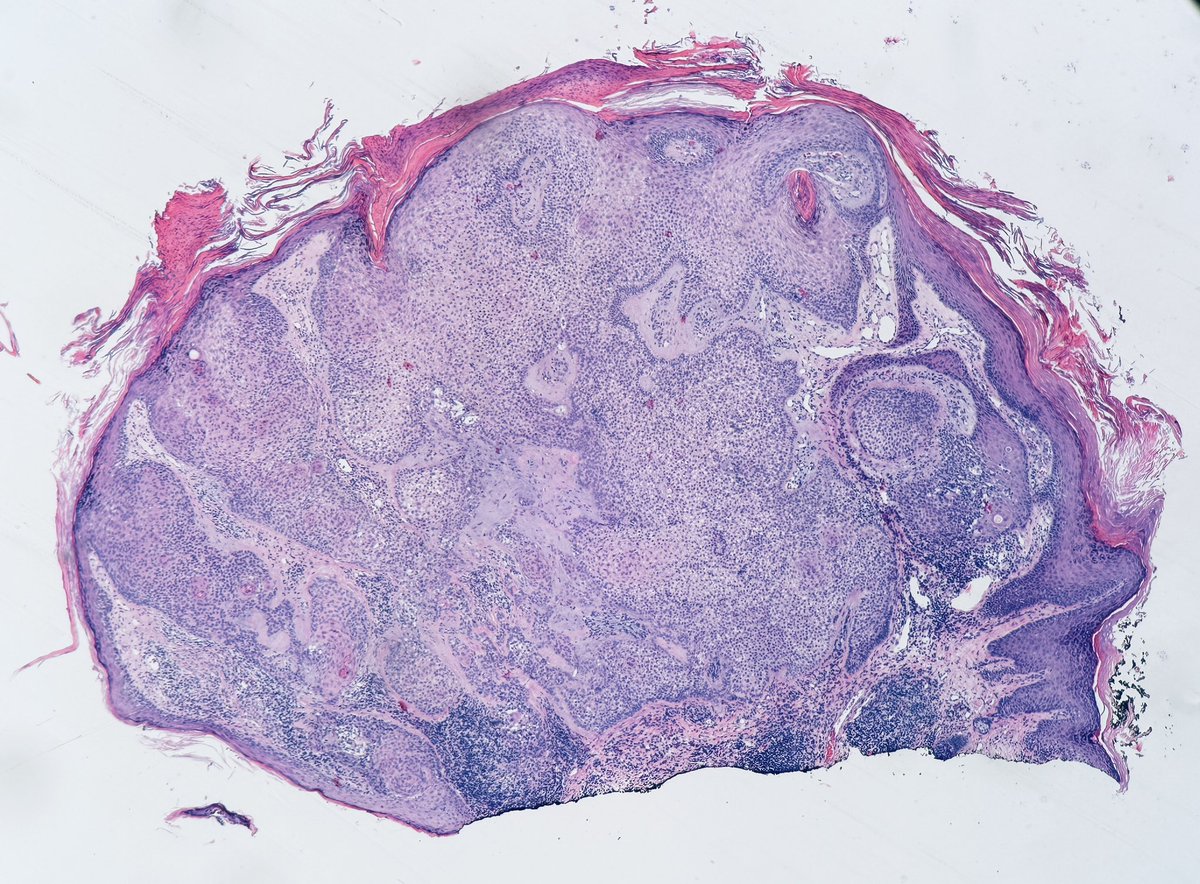

65 year old man posterior auricular neck deep dermal nodule. easy peezy?#dermpath #PathTwitter #dermatology Etan Marks, DO @ArjunRamaiya1 Lorand Kis Olaleke Folaranmi Tristan Rutland MBBS FRCPA IFCAP Trish Stratus Marcelasaeblima. Allison Osmond MD MSc FRCPC Ahmed Alomari, MD Gonzalo De Toro